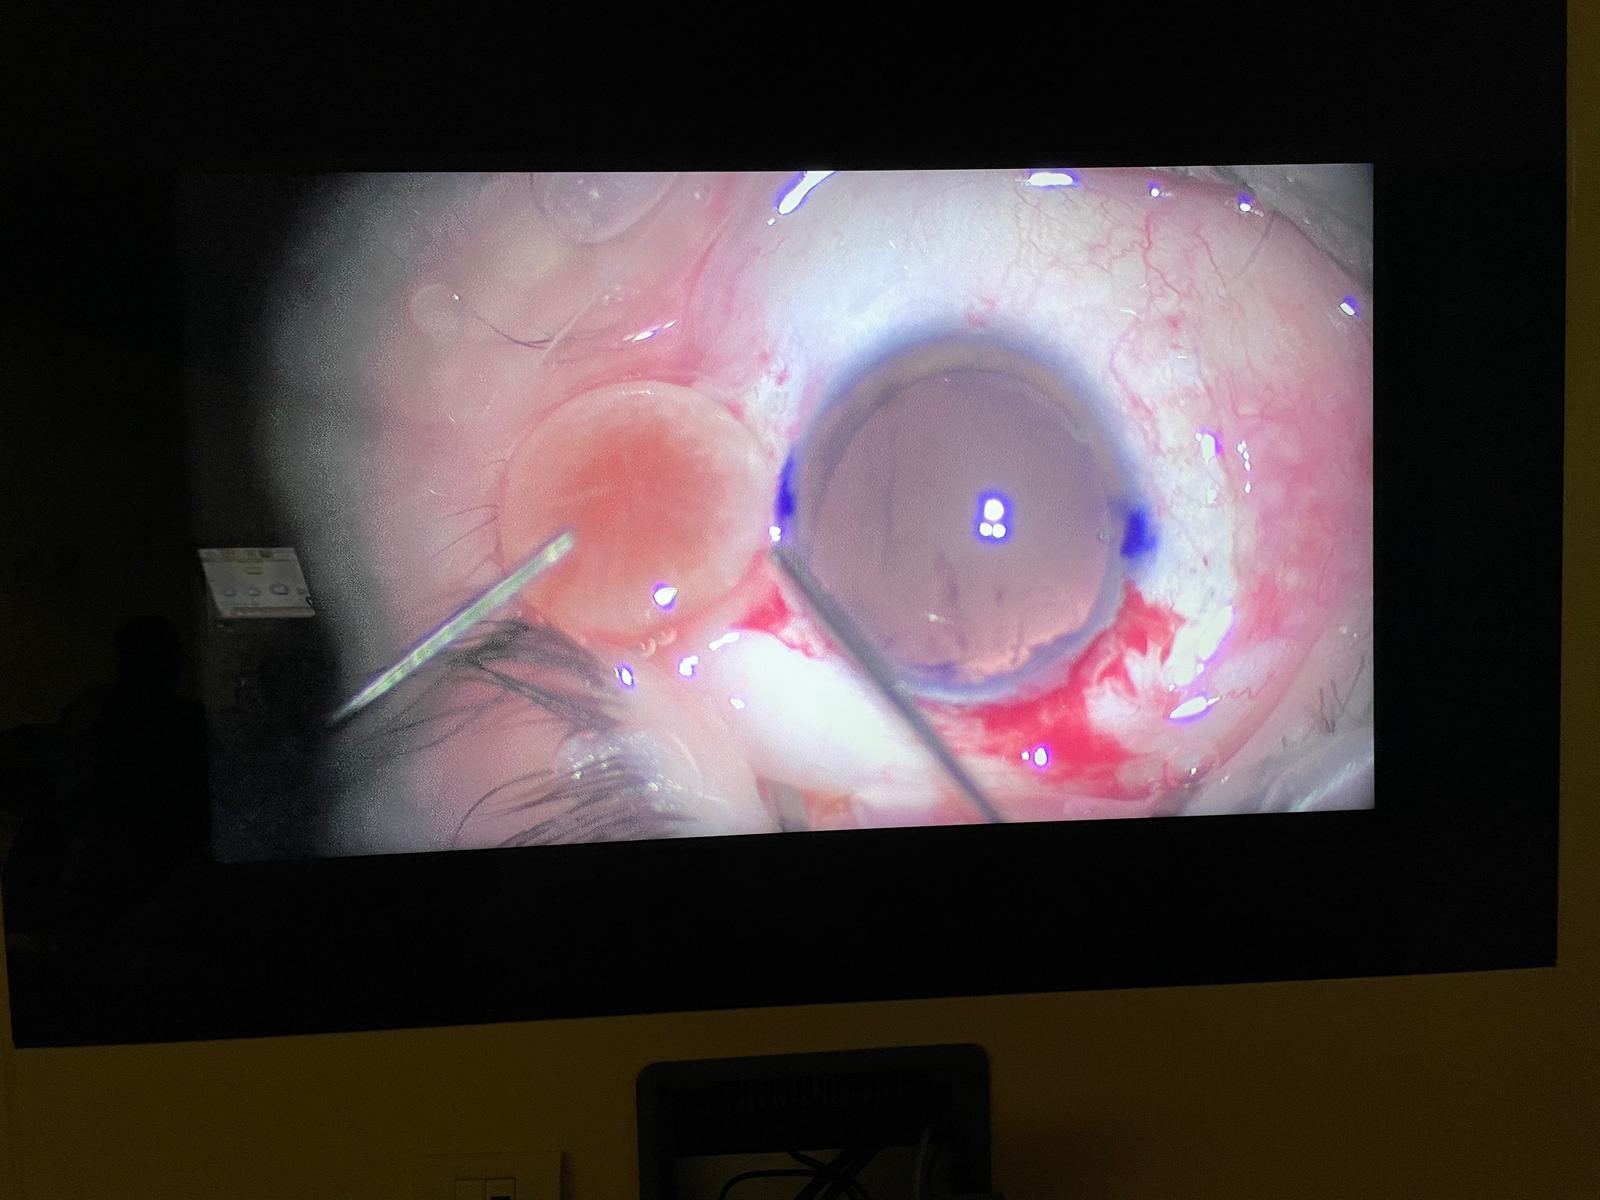

Cazul prezentat aici, deși pentru dr. Ozana Moraru nu a fost unul foarte deosebit, a fost, în schimb, pentru tinerii colegi, specialiști sau rezidenți, care au asistat la operație și, cu siguranță, a fost și pentru pacientă, victimă a violenței domestice, complet nevăzătoare din cauza traumatismelor repetate în zona feței și a ochilor, care au dus la cataractă hipermatură cu subluxație dein cristal la ambii ochi, unul fiind definitiv pierdut, prin glaucom secundar absolut. Legat de tinerii medici observatori, au avut ocazia să vadă o tehnică chirurgicală mai rar efectuată în zilele noastre, fiind mai veche, dar mereu actuală în aceste situații: tehnica intra-capsulară, prin care cristalinul opac și deplasat este extras “în bloc”, pe o incizie de 7-8 mm, care necesită a fi “cusută”, iar cristalinul artificial este unul special, adaptat lipsei de suport, trebuind prins prin diverse tehnici, fie la peretele ocular, fie la iris.

Fotografiile ochiului de azi, din prima zi postoperator (ultimele patru foto), arătau excelent, cu corneea fără pic de edem și cristalinul artificial perfect centrat și, mai mult decît atât, după consultație, stând în sala de așteptare fără pansament, pacienta se uita la televizorul din sală și comenta cu fiica ei ceea ce vedea acolo!